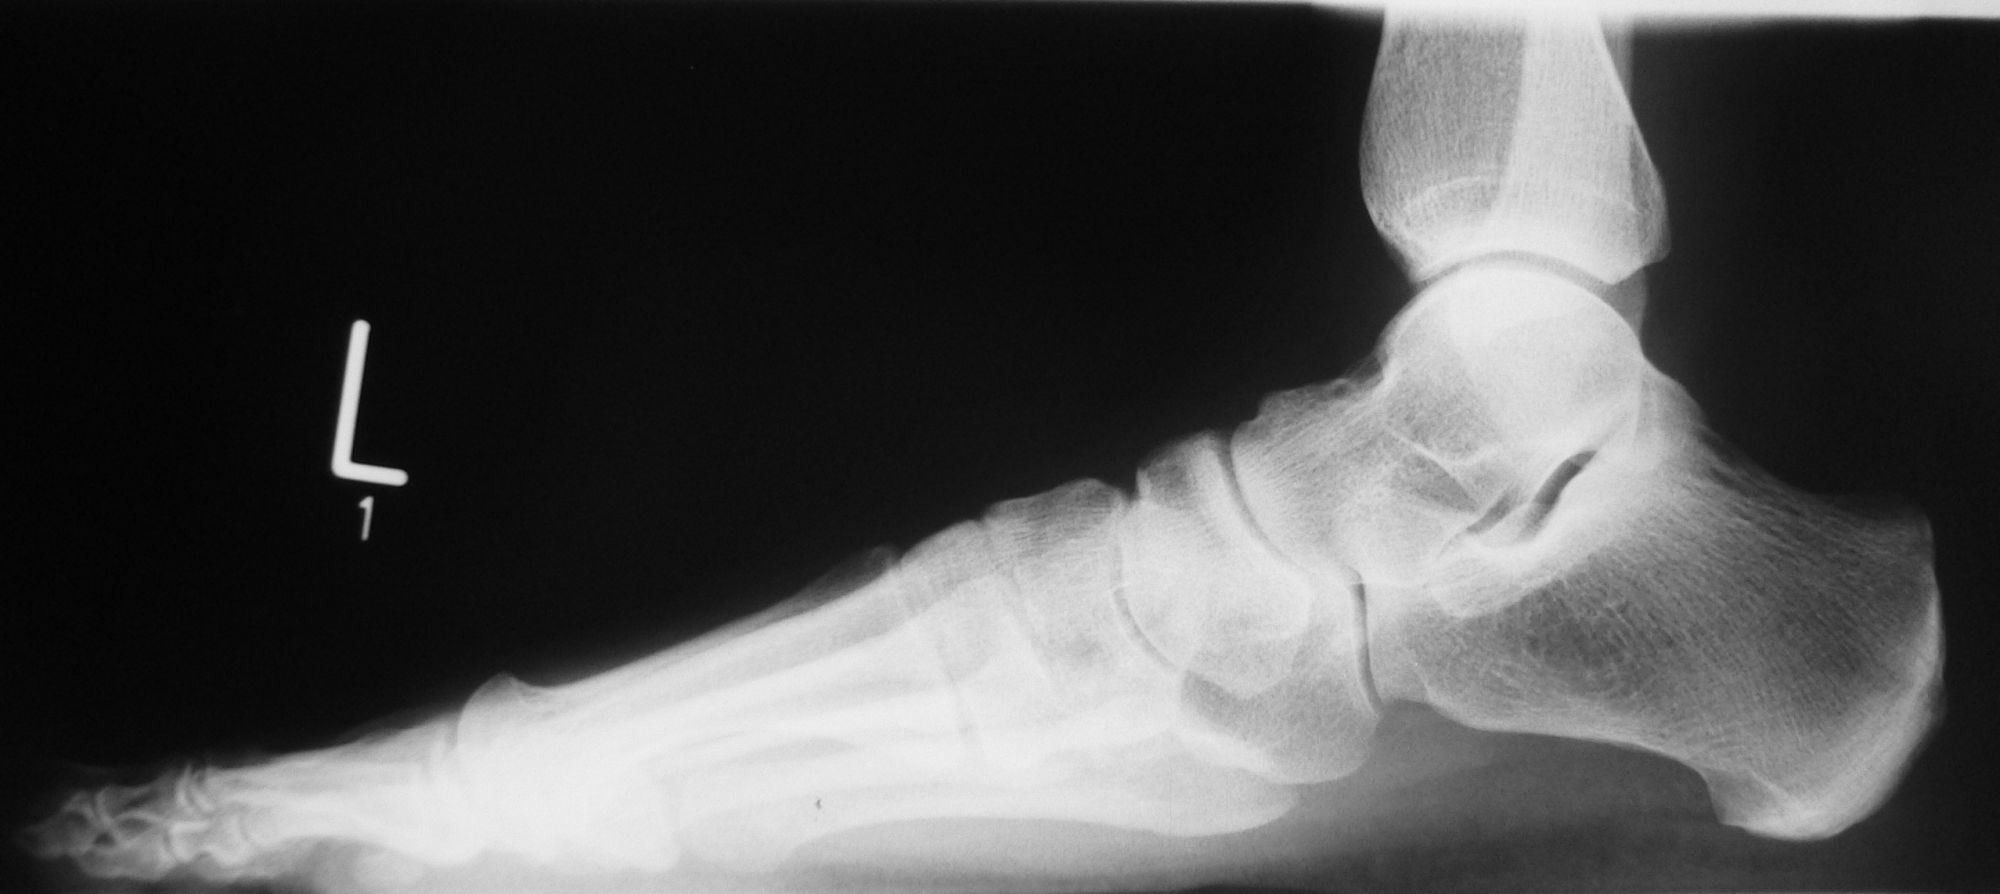

Röntgenaufnahme des Fußes (unter Belastung) in dorsoplantarem, seitlichen und schrägem Strahlengang (Abb. 1a-c).

Beurteilung des ersten Intermetatarsalwinkels (IMA), des Hallux valgus Winkels (HVA), des distalen (Distal Metatarsal Articular Angle, DMAA) und proximalen Gelenkflächenwinkels der Grundphalanx (Proximal Phalangeal Articular Angle, PPAA). Möglicherweise muss die Arthrodese des TMT-1-Gelenks mit weiteren distalen Eingriffen zur Korrektur des Gelenkwinkels kombiniert werden (z.B.: retrokapitale Osteotomie oder Grundphalanxosteotomie).

Zur Vollansicht bitte die Bilder anklicken.

Abbildung 1a

Abbildung 1b

Abbildung 1c